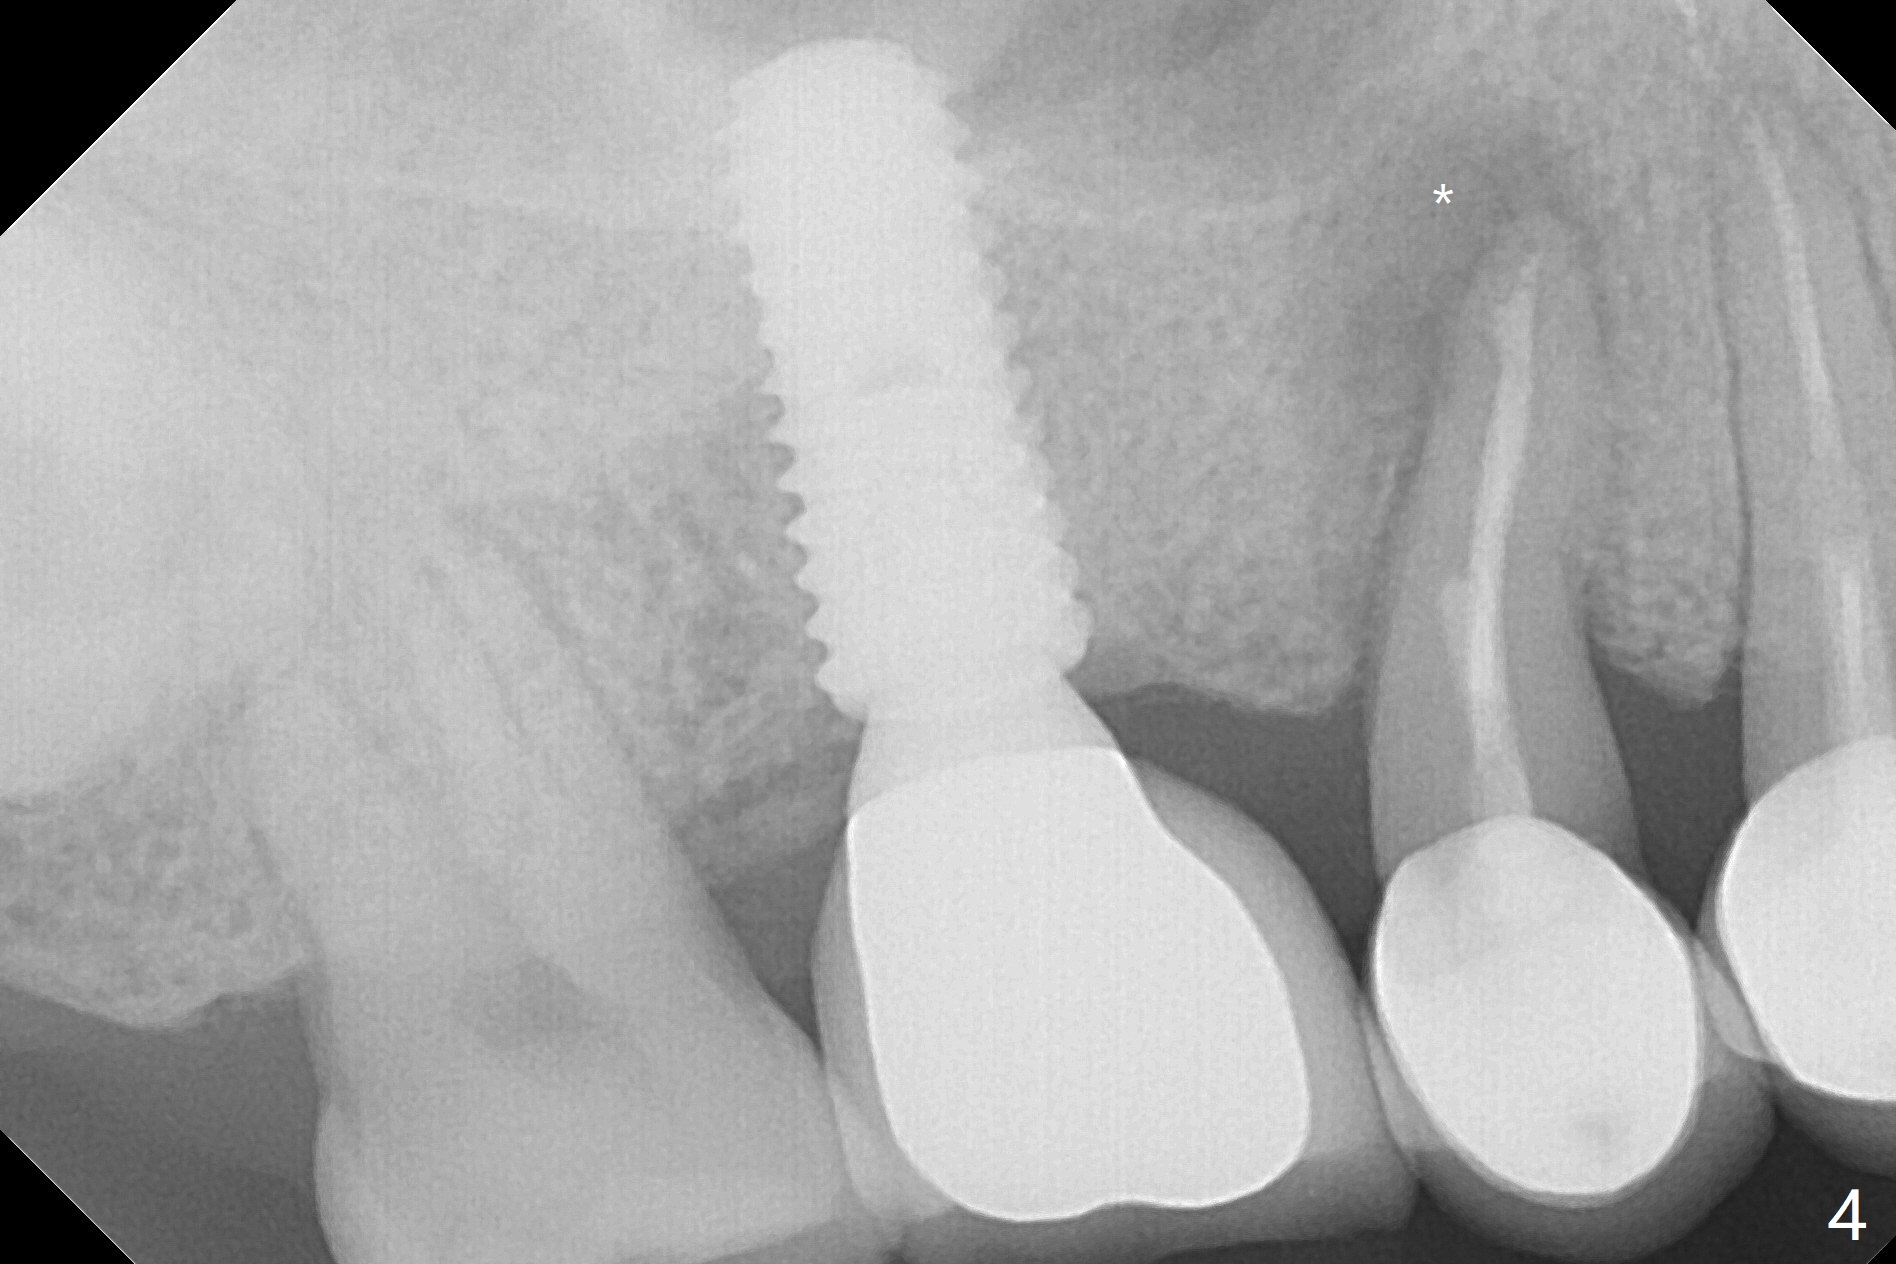

Crown/Implant Ratio

A 53-year-old man has signs of bruxism (Fig.1 diastema *) and root fracture or RCT failure at #4 (Fig.4 (large PARL *)). The RCT failure is related to overload of the affected tooth, which is in turn partially due to infraocclusion of the neighboring implant crown (Fig.1 arrows (implant positioning not ideal)) and partially to due to partial edentulism (Fig.2 missing teeth #14 and 18). For long term, limited ortho will be performed to upright and distalize the tooth #15 (Fig.3 arrow), followed by implants at #14 and 18. For now, the tooth #4 will be extracted (Fig.5), followed by osteotomy in the distal slope of the socket with guide (Fig.6 to get good trajectory). To place a bone-level implant (Fig.7 green), an abutment (blue) with long cuff (pink) is to be used. With poor implant/crown (white) ratio, stress occurs at the junction of the implant/abutment (red arrow), resulting in easy abutment screw loosening. In contrast, stress may be applied to directly to a tissue-level implant (Fig.8 arrow) with less likelihood of abutment screw loosening. The implant/crown ratio improves by approximately 5.5 mm. The roots of the teeth #15 and 16 are so close to each other that interference may occur when the tooth #15 is being uprighted (Fig.9). The empty socket of the tooth #4 is wide buccopalatal (Fig.10); the buccal plate is resorbed coronally (Fig.10 <) so that a 4.5 or 5 mm diameter implant should be placed palatal (Fig.11). Use sticky bone to repair the buccal plate defect and PRF membrane or plug for sinus lift. Following #15 uprighting and distalization, a 5x10 mm implant will be placed at #14; the ridge is triangular (Fig.12 <) so that bone trimmer is needed. A 10 mm long implant will be placed at #18 (Fig.14) to avoid perforating to the submandibular fossa (Fig.13 *).